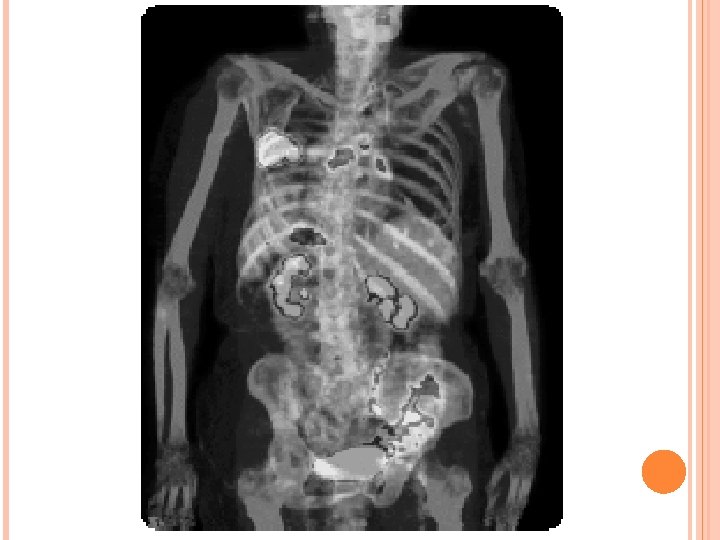

Radiografie PET (Tomografie cu emisie de pozitroni) Obţinerea unei radiografii care oferă imagini a tumorilor maligne din tot corpul. O radiografie PET ar trebui efectuată înainte de operarea tumorii pulmonare şi radioterapia radicală, pentru a vă asigura de eficienţa unui tratament curativ (radiografia PET este mai exactă decât tomografia computerizată). Radiografie PET poate fi folosită totodată pentru a investiga un cancer suspectat, dacă diagnosticul nu a fost posibil folosind alte teste. Pentru evidenţierea celulelor canceroase active se injectează un marker radiologic. Radiografia este nedureroasă, silenţioasă şi nu veţi fi introdus în întregime în aparat în timpul examinării. Spută O analiză de spută poate ajuta la stabilirea existenţei infecţiei sau a sângelui în spută. Acest test se poate face în spital sau în regim ambulator. Ultrasunete Este o radiografie nedureroasă care foloseşte ultrasunetele pentru vizualizarea interiorului corpului. Se foloseşte în examinarea rinichilor, ficatului şi plămânului. Este utilizată adesea pentru a determina existenţa lichidului în plămâni.

Radiografia toracelui anterior si cea laterala evidentiaza o formatiune opaca in plamanul stang, cu extindere pleurala, cu ingrosarea apicala a pleurei si o zona cicatriceala in lobul superior. La computer tomograf se poate vizualiza de asemenea aceasta formatiune si extinderea si dimensiunile ei (10. 8 X 4. 1 cm). Mai mult decat atat, se sesizeaza o ingrosare a periostului coastelor adiacente. RMN-ul cu contrast aduce in atentia medicilor adenopatia supraclaviculara stanga si subliniaza extinderea pana la nivelul pectoralului mare a formatiunii, respectiv in profunzimea parenchimului pulmonar. Diagnostic?